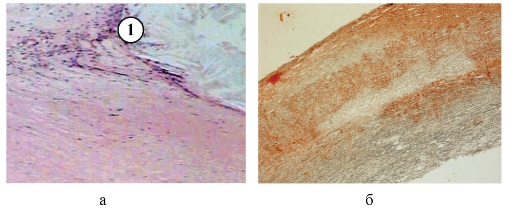

Медицинские исследования: эластическая псевдоксантома